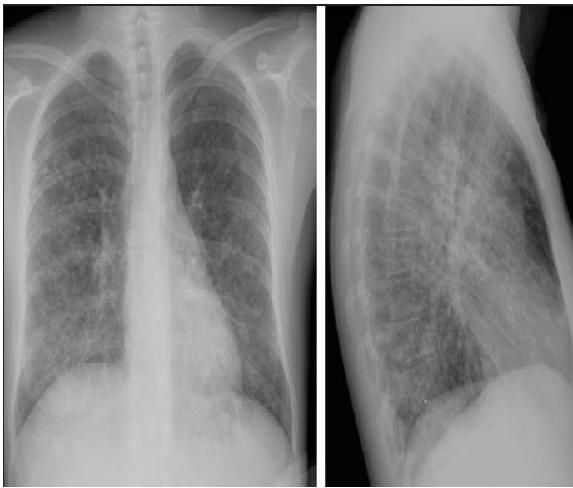

A review of chest radiographs from 50 AIDS patients with documented disseminated histoplasmosis revealed abnormalities in 23 patients, most commonly diffuse nodular, linear, or irregular opacities.8 Less commonly, airspace opacities, small pleural effusions, adenopathy, and Kerley B lines were identified. In 27 patients, the chest radiographic findings were considered normal despite clinical or laboratory evidence of pulmonary disease in 4 of these patients.8

Chest radiographs from a patient with disseminated histoplasmosis are shown in the Figure.

Figure – Reticulonodular infiltrates are evident in these chest radiographs from an HIV-infected patient with disseminated histoplasmosis.